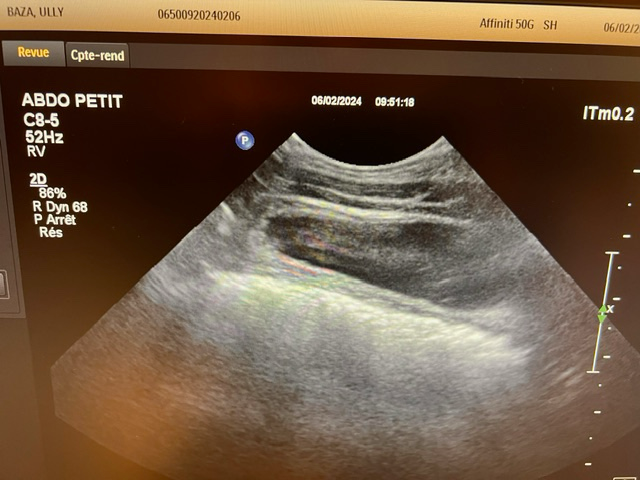

흉부 엑스레이상에서는 교통사고와 관련한 특별한 이상이 관찰되지 않습니다.

초음파 검사의 경우 초음파를 직접 본 사람이 아니면 찍어놓은 사진으로는 아무런 판단을 할 수 없고 해서도 안됩니다.

주치의의 판단이 가장 정확한 판단이겠으나 지현형으로 장기 손상이 일어나는 경우가 종종 있기 때문에 증상이 지속된다면 복부 초음파 검사를 다시 받아볼 필요가 있어 보입니다.